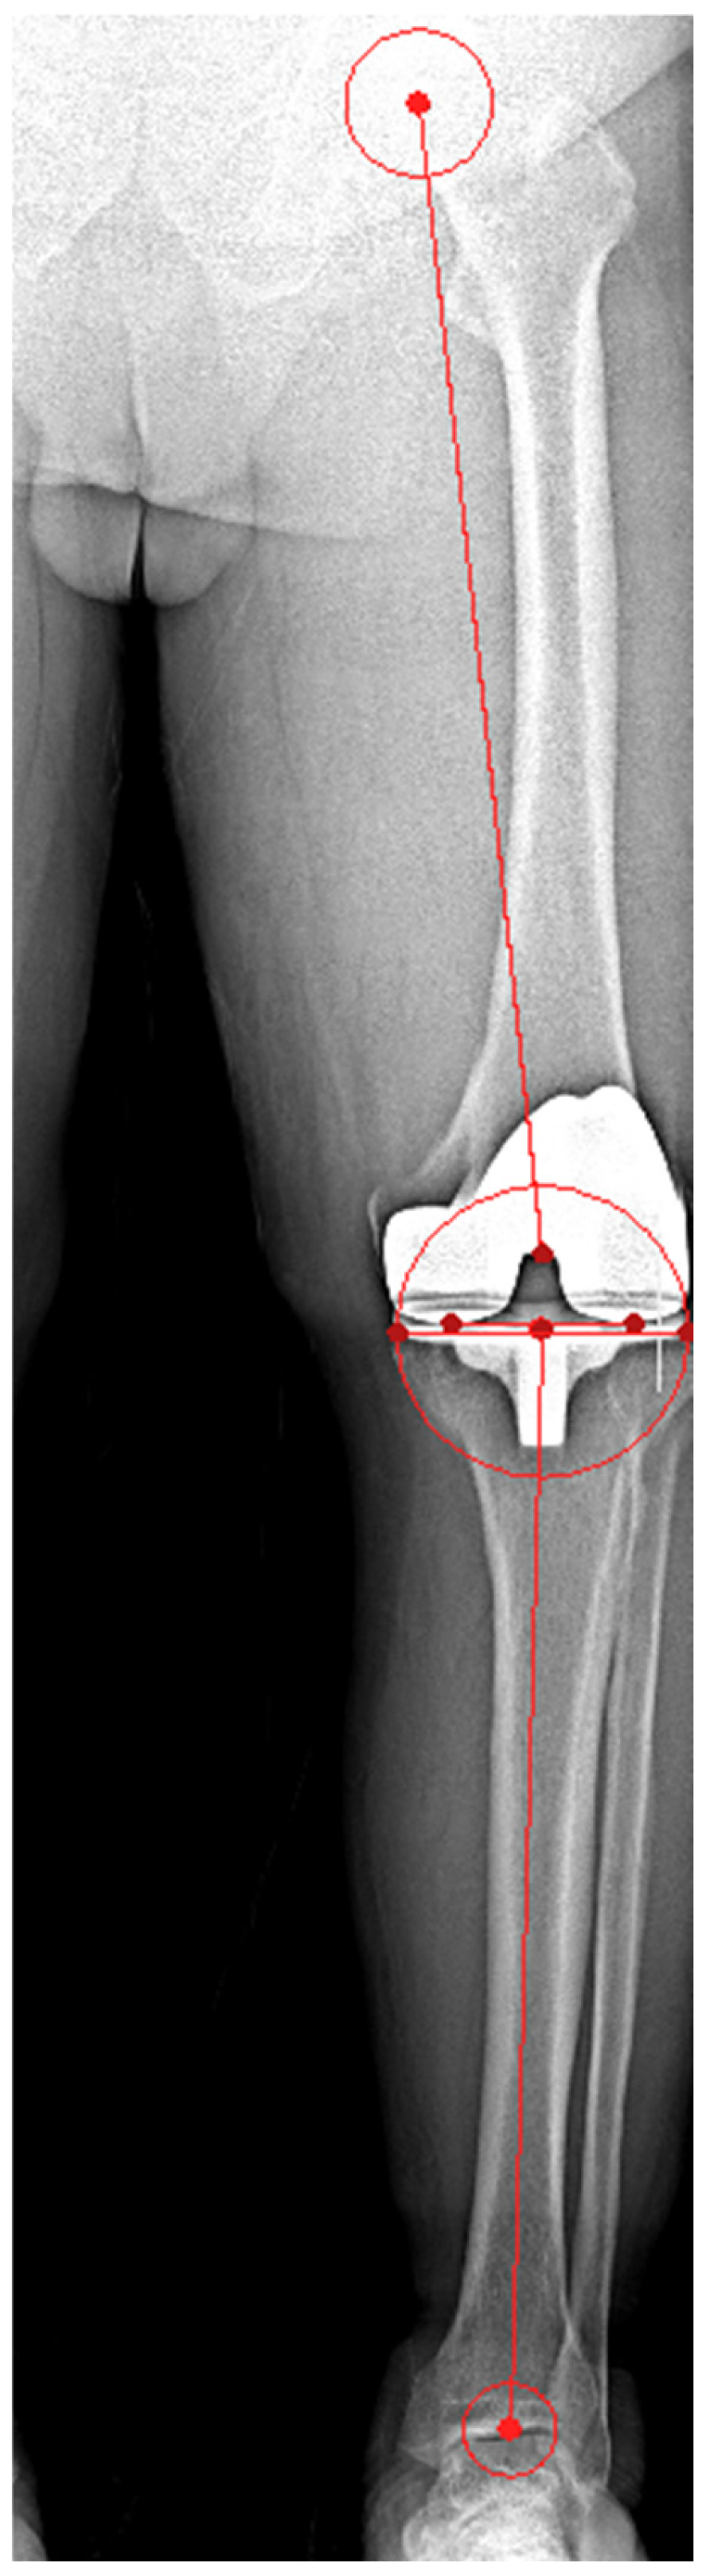

| HKA angle | |||

| Value (°) | 59.2 ± 14.2 | 47.6 ± 12.4 | 0.004 |

| Outlier (n, %) | 119 (36.3) | 23 (7) | <0.001 |

| FCA | |||

| Value (°) | 89.7 ± 1.9 | 89.8 ± 1.5 | 0.453 |

| Outlier (n, %) | 39 (11.9) | 14 (4.3) | 0.002 |

| TCA | |||

| Value (°) | 89.1 ± 1.9 | 89.7 ± 1.6 | <0.001 |

| Outlier (n, %) | 42 (12.8) | 23 (7) | 0.03 |

| FSA | |||

| Value (°) | 85.0 ± 4.4 | 86.9 ± 3.0 | <0.001 |

| Outlier (n, %) | 189 (57.6) | 108 (32.9) | <0.001 |

| TSA | |||

| Outlier (n, %) | 95 (29) | 123 (37.5) | 0.12 |